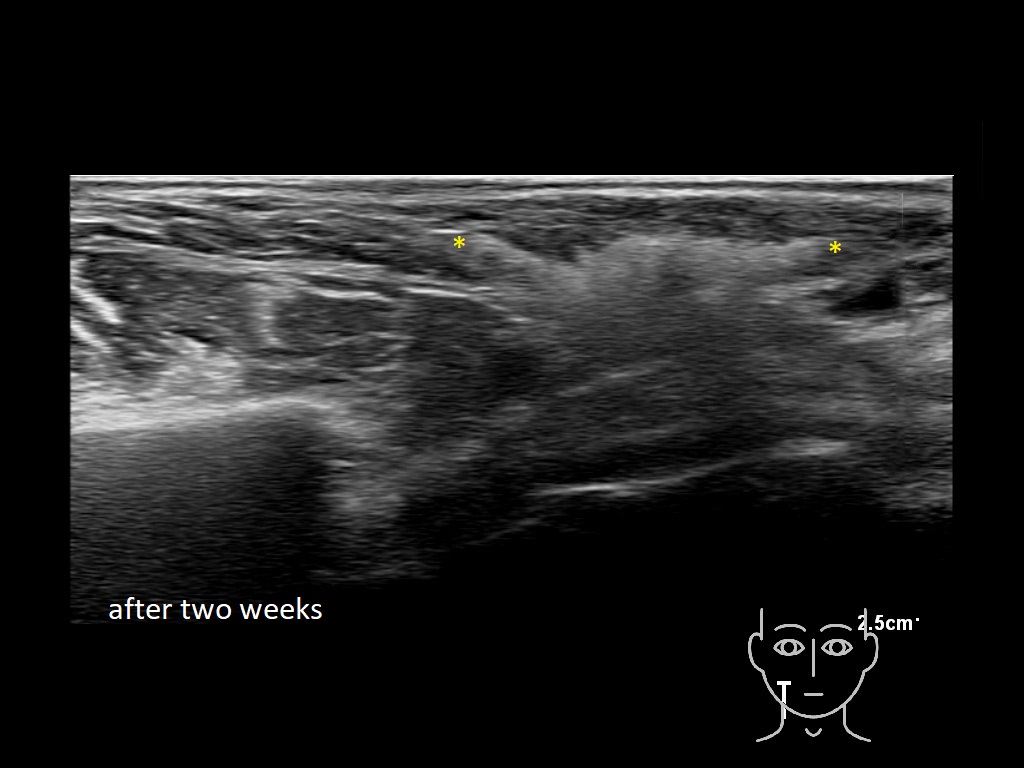

haca 0

HAca 10a